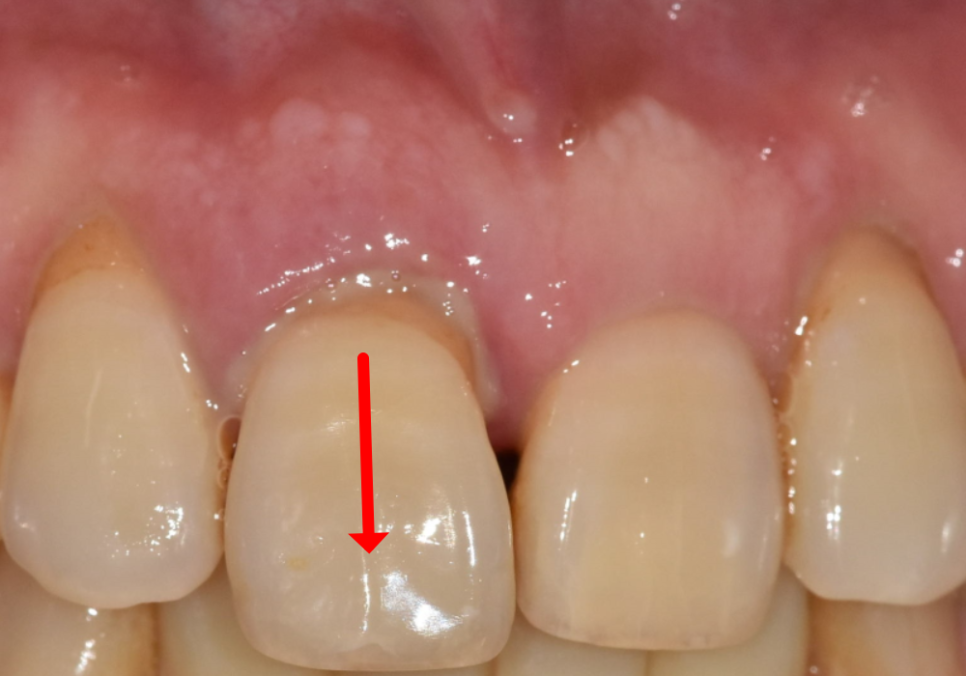

얼마 전 저희 치과를 찾으신 환자분의 사례예요.

위에 앞니 하나가 자꾸 내려와서 보기 싫고

무엇보다 흔들림이 심해 내원하셨어요.

입안을 살펴보니 위 가운데 앞니(#11)가

옆 치아들에 비해 확연히 아래로 내려와 있었어요.

그러다 보니 치아가 삐뚤어 보이는

느낌이 드는데요~

외관상 보기 좋지 않은 것도 문제지만,

사실 그보다 더 큰 본질적인 문제는

'잇몸'에 있었습니다.

잇몸 주위가 빨갛게 부어 있었고,

살짝만 눌러도 고름이 맺힐 정도로

염증이 심한 상태....